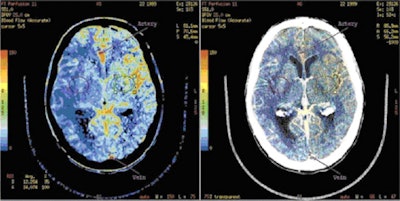

![]() |

| An example of GE's CT perfusion analysis software, based on the deconvolution method of perfusion calculation. Image courtesy of GE. |

He also noted that the often subtle, but sometimes significant, differences between manufacturers' technologies are an important consideration in x-ray exposure. For example, GE, Philips and Toshiba use a deconvolution method to calculate perfusion values, whereas CT scanners made by Siemens rely chiefly on the slope method.

"With deconvolution, you can have a high image frequency and a lower tube current, whereas with the slope method, the accuracy of the measurement is more dependent upon the accuracy of two particular readings," Miles said. "It is therefore useful to have a lower frequency and a high tube current to get accurate measurements from the two time points when using the slope method."